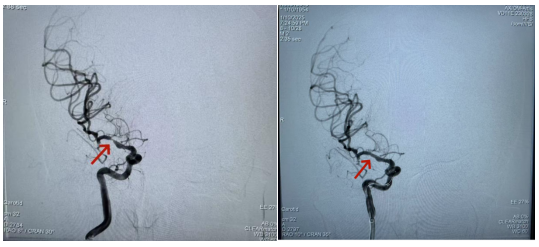

祸不单行,近日唐女士多次出现左侧肢体无力、言语不清、口角流涎,虽数分钟后可自行缓解,但症状反复出现且不断加重。病情复杂的唐女士在北京市垂杨柳医院肾内科病房住院治疗期间,左肢瘫痪,言语不清再次发作且不能缓解。医院神经内科接到会诊申请后立即启动院内急会诊,根据病史、症状、体征,明确诊断唐女士为缺血性脑卒中,给予抗血栓药物治疗后唐女士的症状有所好转。但随后的头核磁结果显示右侧大脑中动脉重度狭窄达95%,这正是导致她左侧肢体无力的“罪魁祸首”,如此严重的狭窄,血管随时可能闭塞,导致病情急转直下。

经过充分评估与讨论,2025年1月10日,神经介入组组长、副主任医师李军,会同副主任医师胡益民,为唐女士实施右侧大脑中动脉支架置入血管成型术。局部麻醉下,患者需保持绝对稳定与配合,这对医生的操作熟练程度和手术精准程度提出了极高要求。术中,为降低造影剂对肾功能的损害风险,医生仅用30ml造影剂,便在短短40分钟内顺利完成手术。

术后,唐女士神经系统症状及体征稳定,肾功能复查无明显恶化,术后4天便顺利出院。局部麻醉、大脑中动脉支架置入、30ml造影剂、40分钟手术时长,这些看似不可能完成的任务,在这位身患恶性肿瘤、肾功能不全、胸腔积液、急性脑梗死的患者身上成为现实。这不仅得益于医院流畅的院内卒中诊治流程、多科室之间的紧密协作,更离不开患者和家属的信任与积极配合。唐女士此次手术的成功,为更多病情复杂的患者带来了新希望,也为神经内科介入团队提出了更高的要求。今后,在脑血管病患者的血管内介入治疗领域,垂医人将持续精进技术,不断迎接新挑战、实现新突破,于绝境中探寻生机,在挑战与突破中砥砺前行。